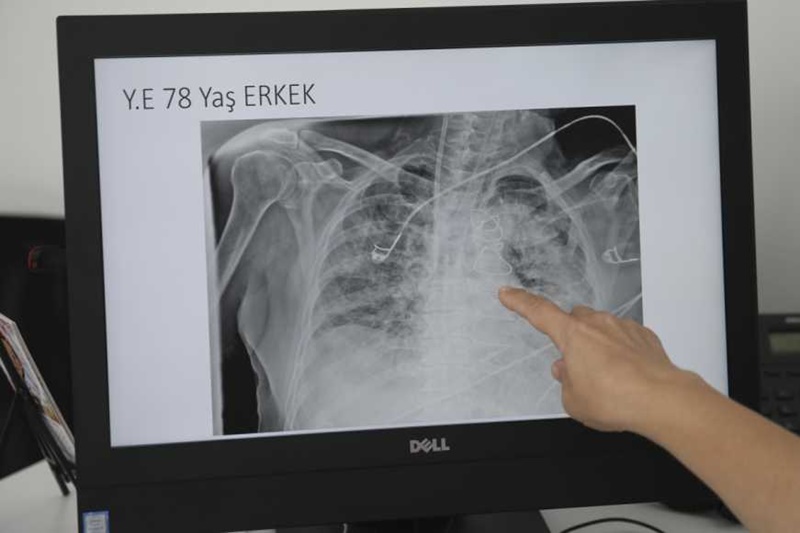

Prvi simptom atipične upale pluća obično je povišena tjelesna temperatura, ne previsoka. Zatim se javljaju suh kašalj, bol u prsima, kratkoća daha, umor, glavobolja. Simptomi su često neobični za upalu pluća. Može doći i do upale mozga, kožnih osipa ili nekog poremećaja svijesti. Prenosi se kapljičnim putem.

Atipična upala pluća krajem prošle godine počela se češće pojavljivati u Aziji i nekim europskim zemljama. U Klinici Fran Mihaljević porast bilježe već nekoliko mjeseci. “Na sreću, prolazi ambulatno ili kroz naše dnevne bolnice, ali ima onih s težim kliničkim formama bolesti, osobito kad govorimo o dječjoj populaciji koji su liječeni bolnički praktički s intenzivnim metodama liječenja u pojedinim situacijama”, rekao je Barišić.